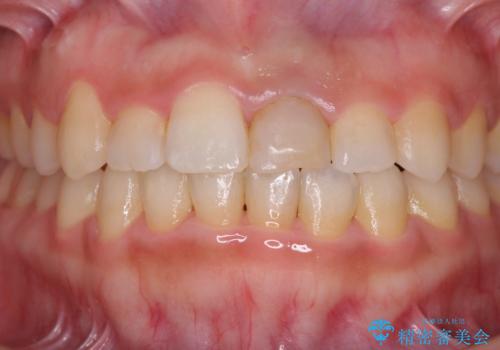

前歯のクロスバイトと変色した歯 ワイヤー矯正とセラミック治療

- 前歯のクロスバイトと神経を取り除いた後に変色してしまった前歯を気にして来院された患者様です。

ワイヤー矯正により矯正治療を行った後に、前歯の補綴治療を行うこととしました。

変色してしまった前歯は、反対側の歯と比べて歯肉が覆い被さっていたため、骨整形を含めた歯周外科処置を行い、歯肉ラインを整えることとしました。

インビザラインでの矯正治療も十分に対応可能でしたが、自己管理の煩わしさから、ワイヤー矯正を行うこととしました。

歯周外科処置を行うかどうかは非常に悩んでいらっしゃいましたが、範囲がそれほど広くないため術後の痛みも強くないだろうということで、処置を行うこととなりました。